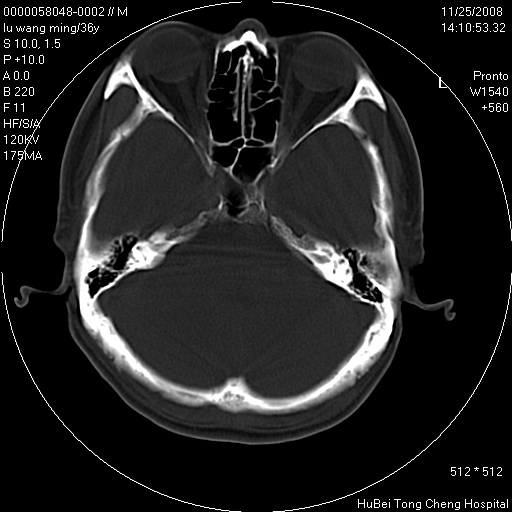

患者 男,36岁。头部烧伤36年伴溃烂,经久不愈。患者几个月大时,倒入火炉不幸烧伤头部,后长期溃烂,经久不愈。

临床诊断:1)头皮烧伤并感染。2)颅骨病损?

颅脑ct轴位平扫(层厚、层距均匀10mm),图像如下:

以骨质破坏为为,边缘呈虫噬样改变,多砂粒样钙钙化或死骨,伴软组织及硬膜外积脓,考虑为结核感染可能性大,建议细菌培养。

额顶局部骨质破坏缺损

患者有明确的病史,且经久不愈,更该考虑软组织化脓性感染,颅骨损害伴硬膜下下积脓

结合病史考虑颅骨慢性骨髓炎

结合病史考虑颅骨慢性骨髓炎伴硬膜外积脓。

结合病史考虑颅骨慢性骨髓炎;但局部见一软组织肿块,用炎症不好解释,应增强除外肿瘤。

骨质破坏,边缘呈虫噬样改变,结合患者明确烧伤史,经久不愈,考虑软组织化脓性感染,颅骨损害伴硬膜下积脓。

结合病史考虑颅骨慢性骨髓炎伴硬膜外积脓,软组织溃烂恶变不排除,建议活检。